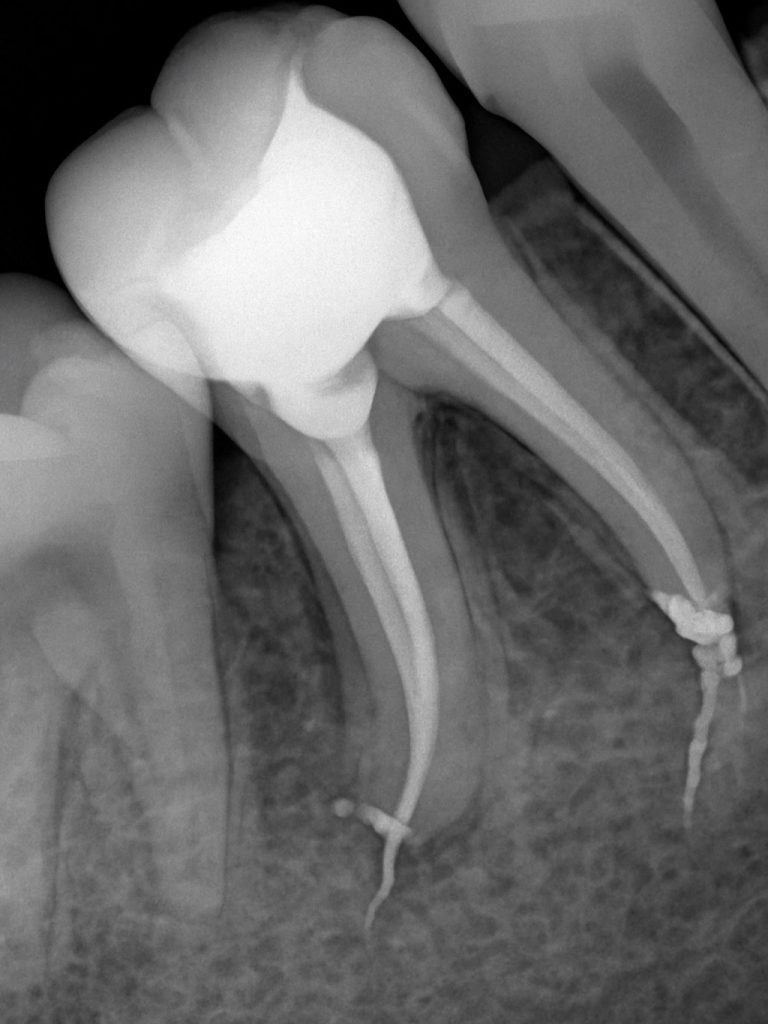

3️⃣ Canal Negotiation & Working Length

All canals were explored using #10 K-files. Working length determined with an apex locator and verified radiographically (Fig 3). The molar exhibited typical MB, ML, and distal canal configuration.

- Fig 3: Working length radiograph.